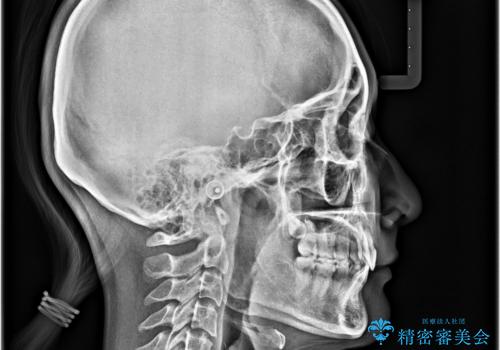

深い咬み合わせは上顎前歯を引っ込ませる大きな障害となるため、咬み合わせの改善が非常に重要となります。やや期間はかかりましたが、当初狙った通りの仕上がりで治療を終えることができました。